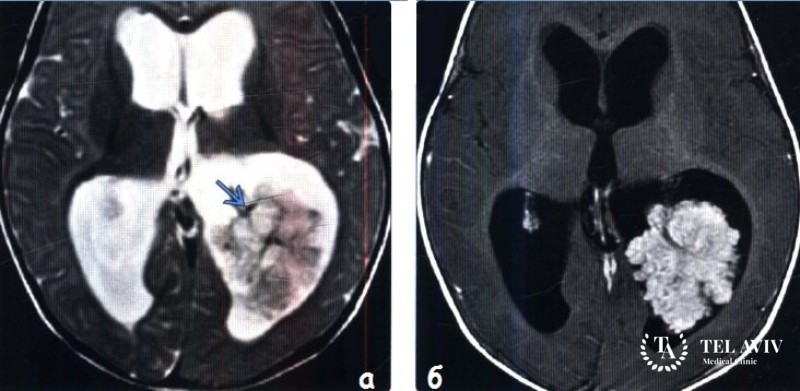

- МРТ или КТ;

С помощью данных способов врач определяет размер и локализацию опухоли и устанавливает окончательный диагноз.